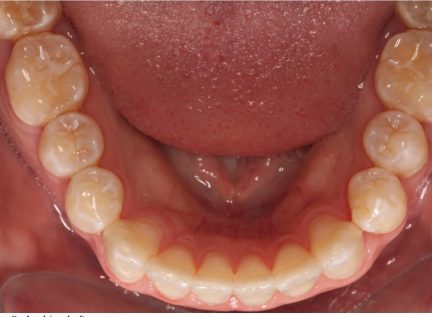

État initial

État final